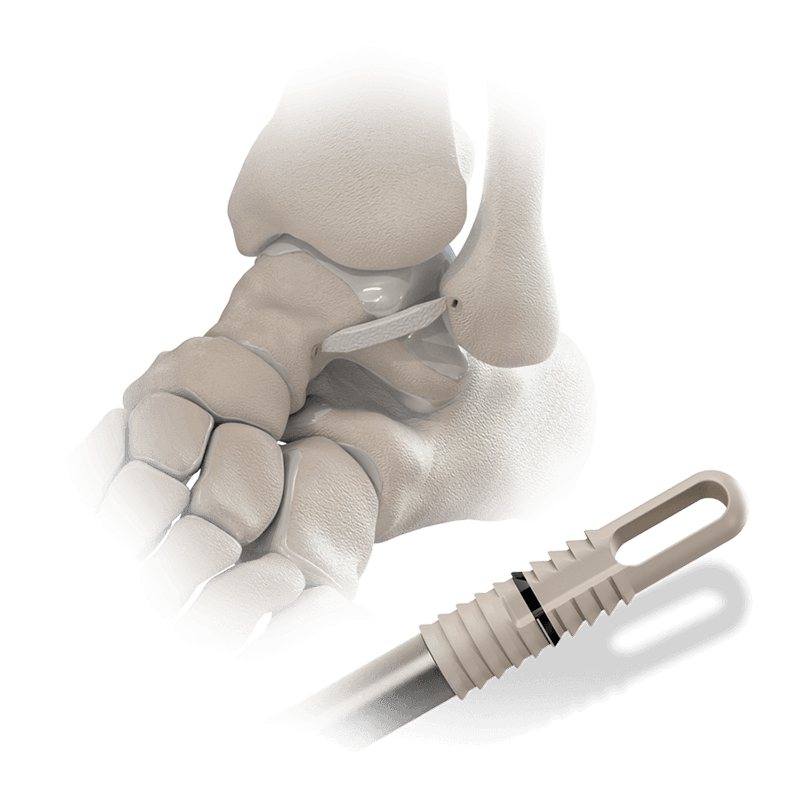

Knotless, Twist-in Anchor for reattaching soft tissue to bone with suture

A radiolucent PEEK anchor with the extended eyelet, designed for use with the BioBrace® 5x250mm scaffold in complex foot and ankle repairs.